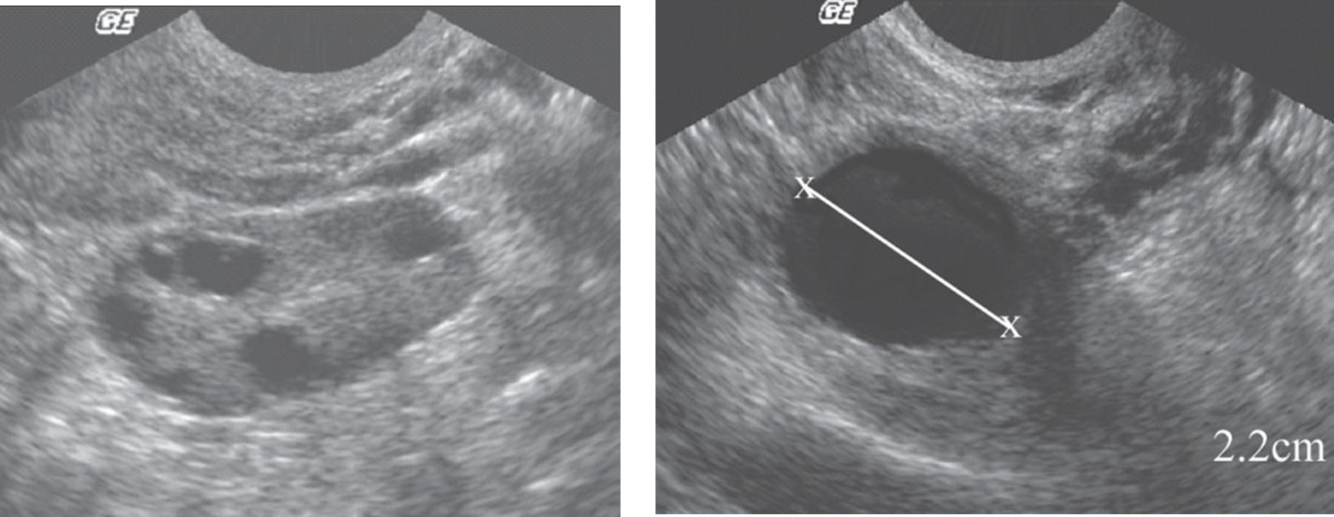

Follicles

Polycystic Ovarian Syndrome“string of pearls”

ovarian volume > 10 cm3